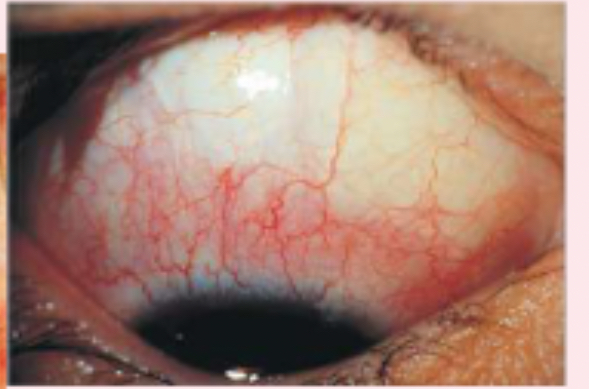

diffuse episcleritis

inflammation of the sclera

subconjunctival hemorrhage

bright red areas of the sclera